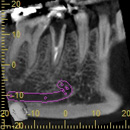

治療前のレントゲン写真。

黄色い線が上顎洞部分です。

黄色と赤の線で囲まれた所に、サイナスリフトによって骨補てん材が注入されています。

サイナスリフト実施7ヶ月後、インプラント埋入を行いました。